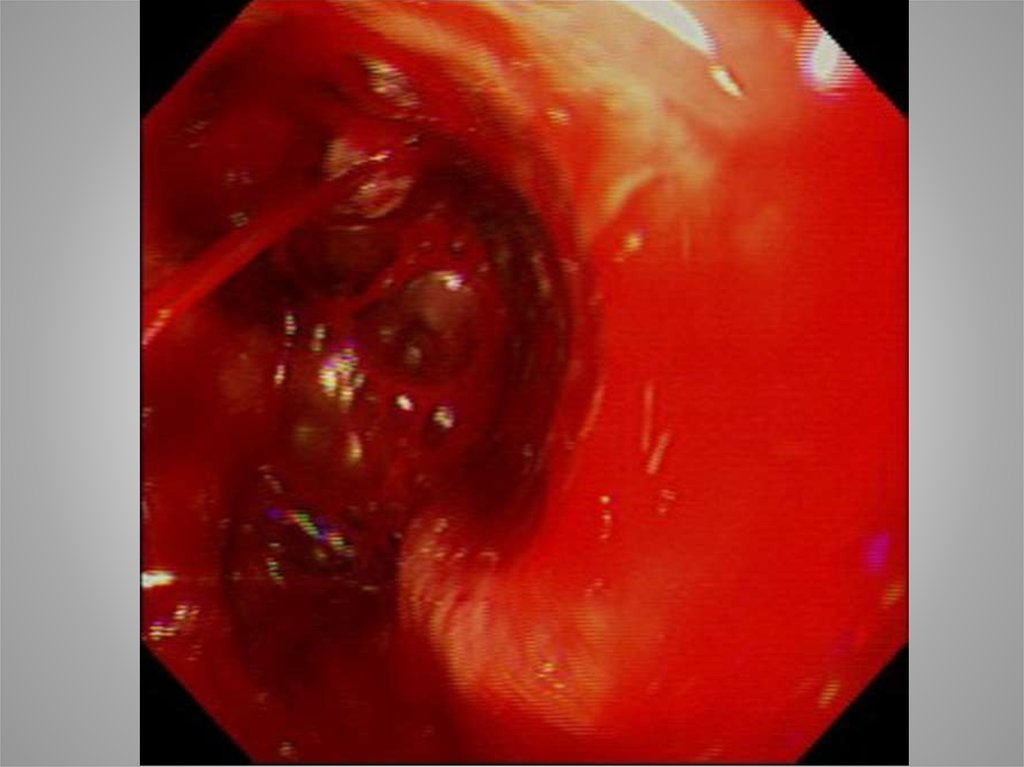

Кровотечение

Форест ?

Эндовазальный гемостаз

Термо- или электрокоагуляция

Аргоноплазменная коагуляция

Клипирование